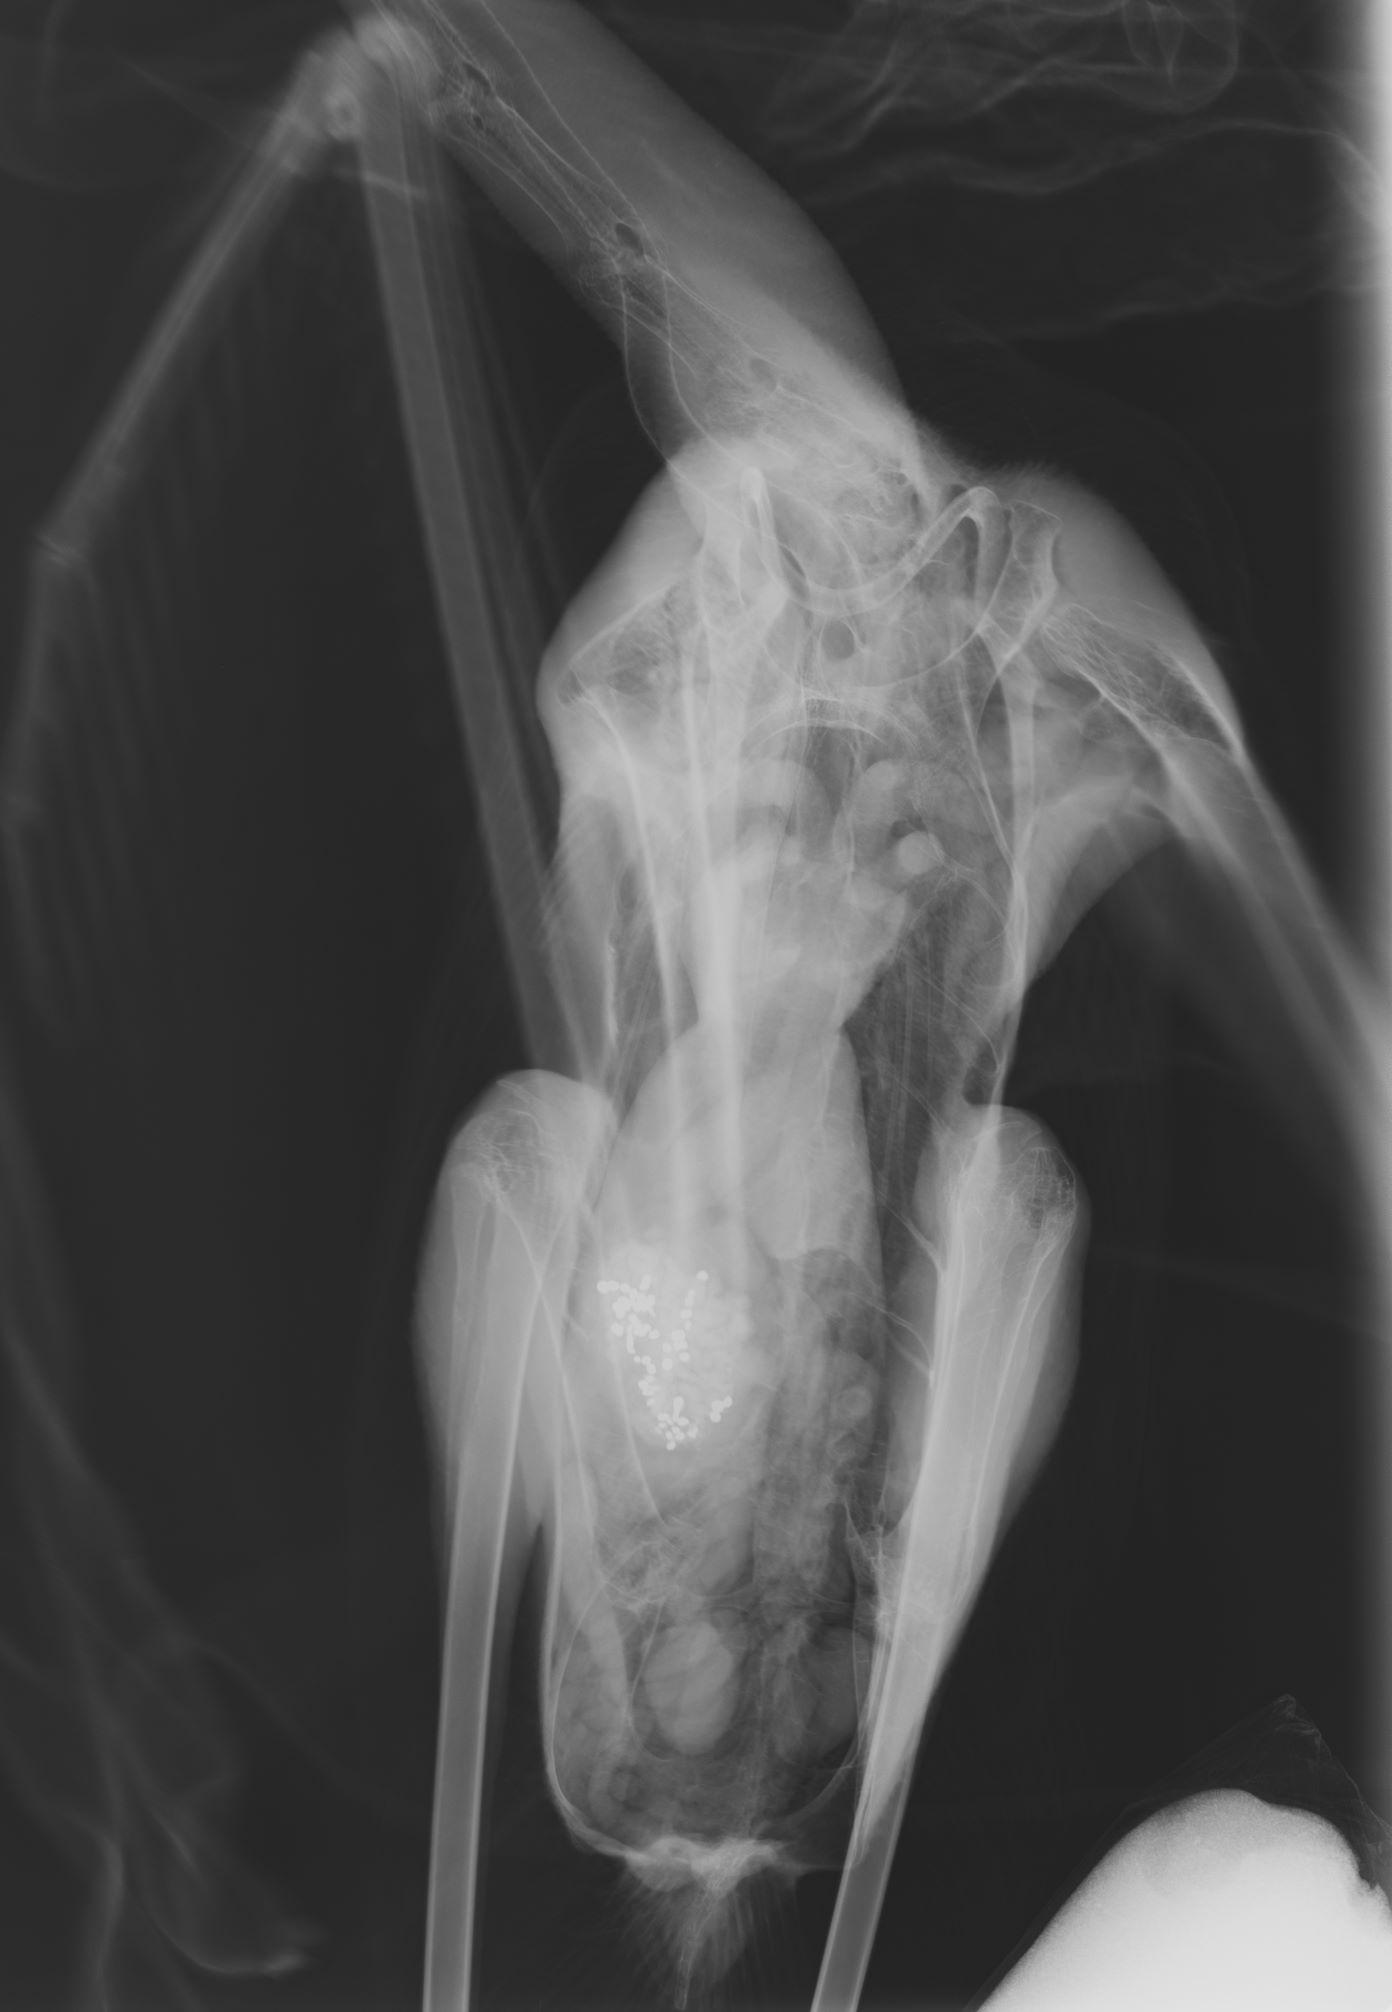

«Παγκόσμια μέρα υγροτόπων σήμερα και αντί να τη γιορτάσουμε πενθούμε!» αναφέρεται στην ανακοίνωση της «Δράσης», όπου τονίζεται ότι μέσα σε μια εβδομάδα, «από 22 έως 29 Ιανουαρίου, τέσσερα φοινικόπτερα (Phoenicopterus roseus) ή φλαμίνγκο όπως τα γνωρίζει ο κόσμος, τα οποία μεταφέρθηκαν για νοσηλεία, είχαν συμπτώματα δηλητηρίασης από μόλυβδο», κάτι που επιβεβαίωσαν και οι ακτινολογικές εξετάσεις δείχνοντας σκάγια μολύβδου στο στομάχι.

Μάλιστα, το ένα από τα φλαμίνγκο που κινδυνεύει, διαπιστώθηκε ότι έχει καταπιεί δεκάδες σκάγια κι αγωνίζεται να επιβιώσει.